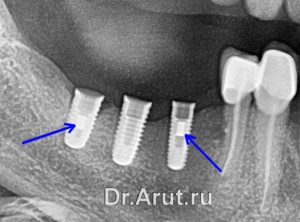

Пациент У. обратился в клинику с жалобами на поломку винтов в имплантатах в области 45 и 47 зубов. Рацементировку коронки на имплантат в области 46 зуба.

Винт 45 зуба был выкручен в помощью высверливания паза и выкручивания ультразвуком. Винт в области 47 зуба не удалось выкрутить с помощью ультразвука, поэтому он был высверлен с помощью сверла (рис.А) через направляющую (рис.Б), резьба очищена с помощью специального инструмента (рис.В).